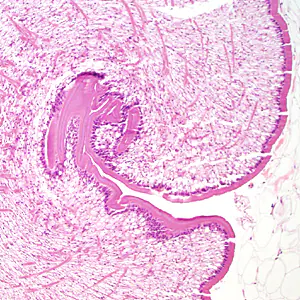

Case #333 – October, 2012

A 68-year-old woman underwent a routine screening mammogram, which revealed calcifications in the right breast. Biopsy specimens were collected and sent to Pathology for histological work-up. Figures A–D show what was observed at 20x, 100x, 200x, and 400x magnification respectively by the attending pathologist on one of the slides stained with hematoxylin and eosin (H&E). What is your diagnosis? Based on what criteria?

Figure B